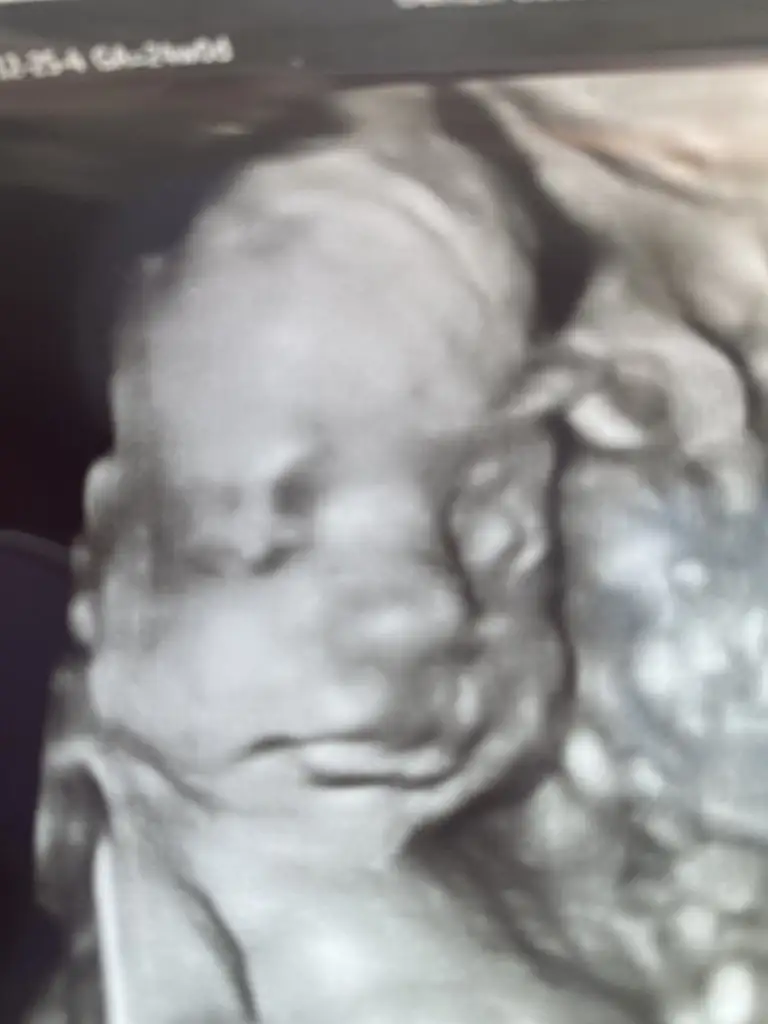

Bugün benim de randevum vardı, 24 haftalık olduğunu gösteren belgeyi aldık idari izin için. Her şey yolundaydı, 29 cm 630 gr olmuş bıdıkko😍😍 ağrılarım için magnezyum yazdı, tablet istedim. Bugünün fotosunu da şöyleee ekleyeyim teyzeler🤩

aiyyy dudaklara bak maşallah 🧡🧡🙏🙏 yanaklar da nasıl etlenmiş, pompiş pompişş

nerdeyse 30 cm lik bir küçük insan 🤩

Yaa o dudaklar ne öyle,dokunmayın keyfim yerinde pozu vermiş baya memnun halinden sanki 🤩🤩🤩